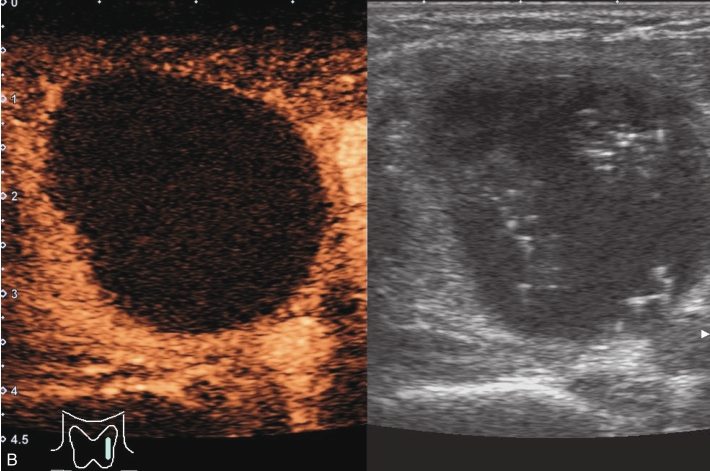

甲状腺左叶中部结节15s开始增强。增强早期与周围正常甲状腺组织呈同步等增强,内部增强不均匀,增强后结节边界清,形态规则,周边可见环状高增强,增强晚期呈不均匀性低增强,见图1-3-10、ER1-3-5。

结节性甲状腺肿超声造影表现为病变多与周围正常甲状腺组织呈同步等或高增强,增强多较均匀,伴有囊性变者,内部可见无增强区,增强后结节边界清,周边可见环状增强,增强晚期呈等或稍高增强,也可呈稍低增强。

图1-3-10 结节性甲状腺肿超声造影图

A.增强早期结节呈同步不均匀性等增强;B.增强晚期呈不均匀性低增强